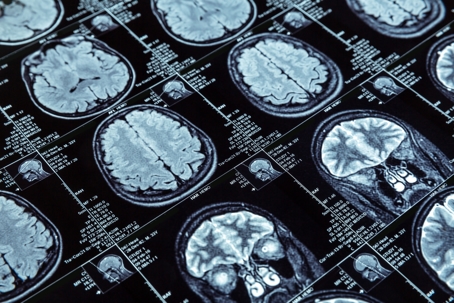

brain scan